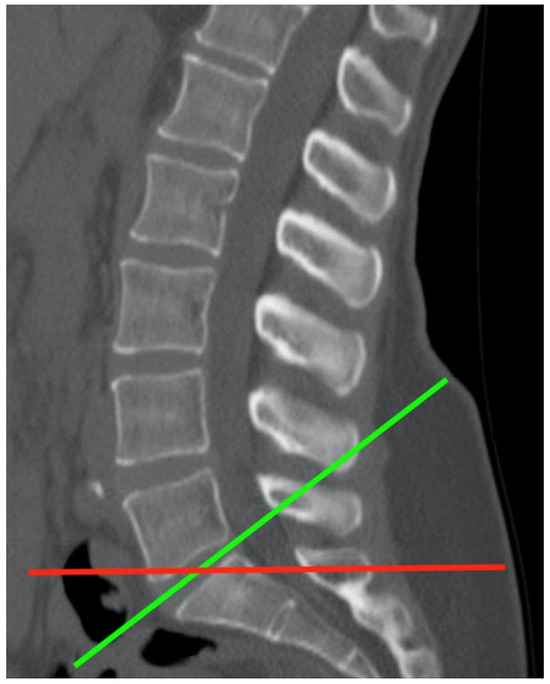

Lumbar Muscle Fatty Infiltration and Atrophy in Patients with Low Back Pain and Degenerative Spinal Pathologies: A CT Imaging Study

by Tess Mardulyn, Arnaud Delafontaine, Patrice Jissendi and Laurent Fabeck

J. Clin. Med. 2025, 14(6), 2125; https://doi.org/10.3390/jcm14062125 - 20 Mar 2025

Background/Objectives: Low back pain (LBP) may be related to intramuscular fatty infiltration (FI), the topography of which has been the subject of only a few studies. Our goal is therefore to determine the importance and topography of FI at the lumbar level and [...] Read more.

Background/Objectives: Low back pain (LBP) may be related to intramuscular fatty infiltration (FI), the topography of which has been the subject of only a few studies. Our goal is therefore to determine the importance and topography of FI at the lumbar level and evaluate its correlation with LBP. Methods: We conducted a retrospective study and compared 254 LBP patients who underwent a lumbosacral CT scan with a sample of 115 healthy subjects, all classified into three age groups (≤35, 36–55, and >55 years old). In CT scan images from L2 to S1, muscle density (Hounsfield unit values ranging from −29 to +150), reflecting intramuscular FI, was measured. LBP was further divided into five subgroups of pathologies. Results: There was a significant difference in muscle density between the small and large circles at the L4/L5 and L5/S1 levels in LBP patients, which was not observed in the healthy subjects. In both LBP patients and healthy subjects, a decreasing density gradient was observed from L2 to S1, with a significant difference in density across age groups. LBP patients exhibit lower muscle densities compared to healthy subjects. Conclusions: In LBP patients, fatty infiltration (FI) of the paraspinal muscles is most pronounced in the lower lumbar region and appears to be localized at the level of muscle insertion. This localized muscle deficit differs from the age-related process of FI and may contribute to the development of LBP and discopathies. Full article